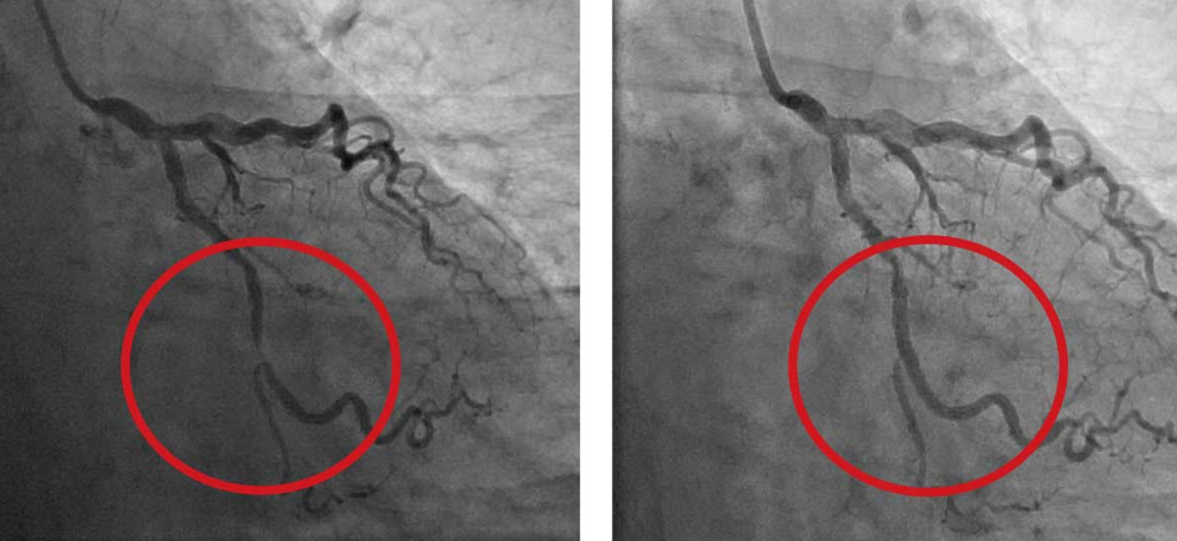

sued.png

7. 그래서 오랜 기간 심장내과에서는 어떤 환자(상황)까지 스텐트를 넣어줄 것인가? 가려서 넣어준다면 무엇을 기준으로 넣을 것인가? 가 논란이었습니다. 아래의 사진처럼 혈관 조영술이나 CCTA에서 끊어질락 말락 하는 아슬아슬한 부위를 본 여러분이라면 과연 어떤 선택을 하시겠습니까?

angioplasty.png